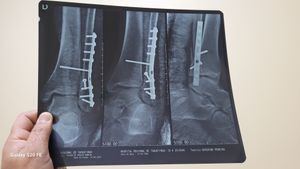

Olá,  sofri um acidente e quebrei o meu tornozelo, coloquei 9 parafusos e uma placa de aço cirúrgico no Hospital de Taguatinga (HRT).